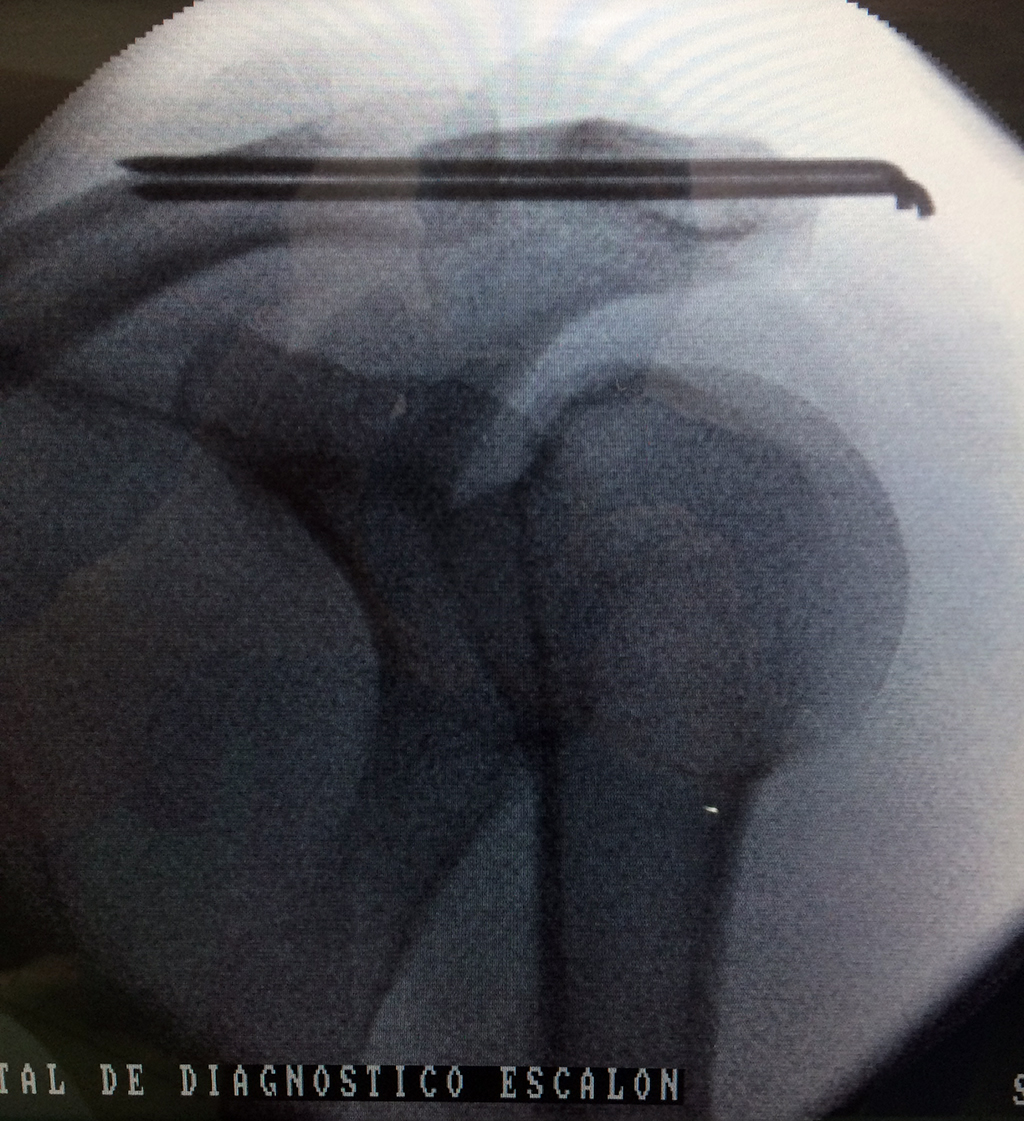

Clavícula

La clavícula es un hueso largo, con forma de "S" itálica, situado en la parte anterosuperior del tórax. Junto con la escápula forman la cintura escapular. Se puede palpar por toda su longitud y se extiende del esternón al acromion de la escápula, siguiendo una dirección oblicua lateral y posterior.